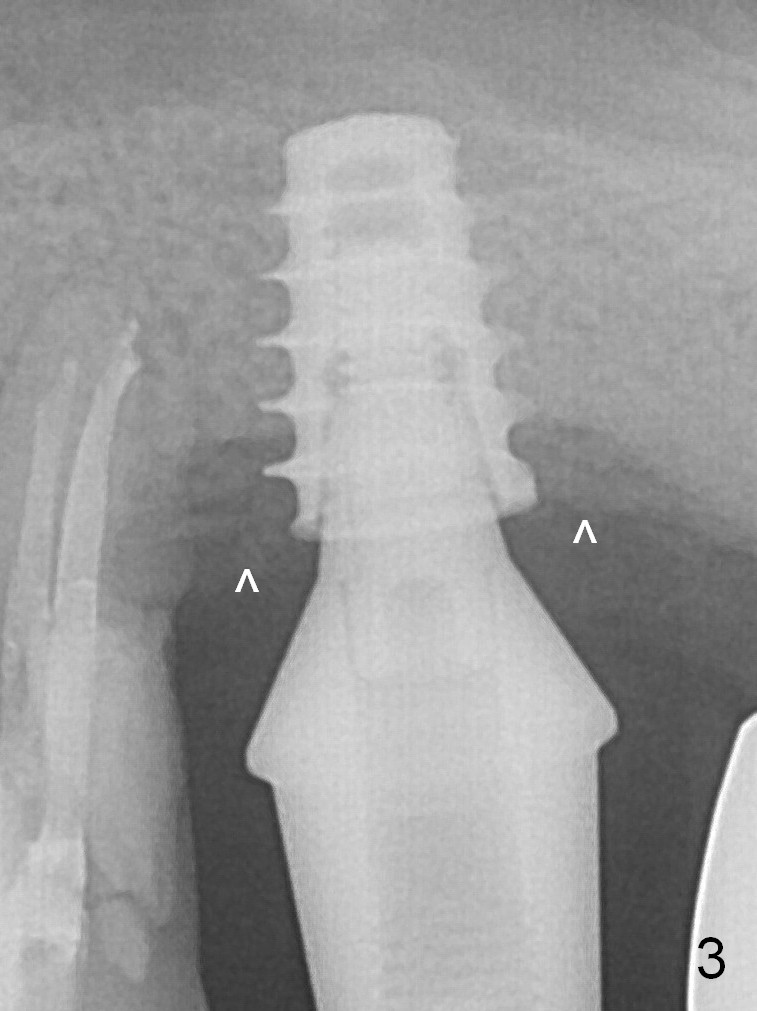

New bone forms apically and coronally 4.5 months postop (Fig.3^). After changing to 6.5x6(2) mm abutment, a new provisional is fabricated so that it can undergo progressive loading for a few months before final impression. The definitive restoration is delivered 7.5 months postop (Fig.5). The bone density apical to the implant becomes apparently denser nearly 5 months post cementation (Fig.6). The bone density in the crest increases 2 years post cementation (Fig.7 *).